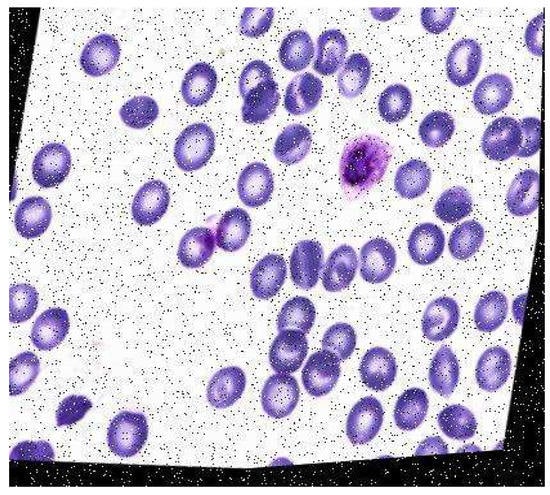

A malaria diagnosis can be made by observing a blood smear obtained from the patient under a microscope slide. The specimen is stained with the Giemsa stain [6]. This is a stain that allows for the differentiation of cells present in the hematopoietic tissue and microorganisms present in it. Since malaria is caused by the Plasmodium parasite that is transferred to the blood, the stain provides a characteristic color to it that aids with its identification [7]. Figure 1 describes the Giemsa-stained blood smear images of a patient infected with malaria.

Figure 1.

Giemsa-stained thin blood smear from malaria patient [8].

The Giemsa stain is the gold standard staining technique for both thick and thin smears to identify blood parasites. The stained blood smear is viewed under a 100× oil immersion objective. The oil-immersion technique is opted for, as it allows the highest magnification to be retained.